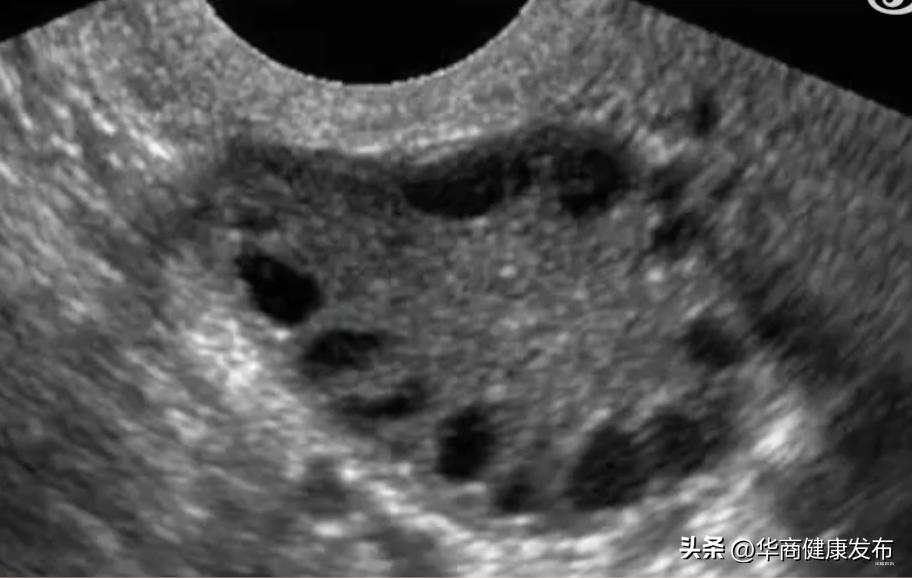

多囊卵巢综合征(PCOS)的历史,最早可以追溯到阿桔初中时期。对于那些接受生理科普知识的人来说,他们知道女性的卵巢位于子宫两侧,负责释放雌性生殖激素、保护卵子,并进行排卵以供受精。然而,多囊卵巢综合征会导致卵巢内同时出现许多小卵泡,但每个卵泡只能长到2-9毫米就停止生长,无法发展成熟卵泡,也无法排出体外,由此引发一系列生理问题。

∧ 阿桔的 B 超检查